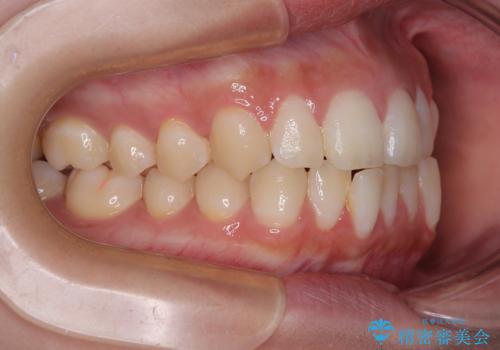

- インビザラインコンプリヘンシブ

- 1年

- 5-10回

診察してみると、下の前歯が並ぶためのスペースが足りないことが、歯並びがデコボコしている原因でした。

下の前歯の歯と歯の間をわずかに削ってスペースを作る(IPR)

奥歯を後ろに動かして、前歯が並ぶためのスペースを確保する